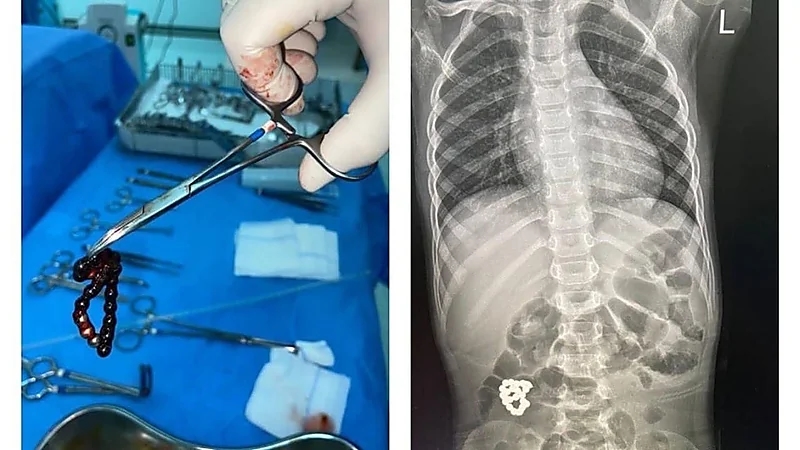

استخراج جسم غريب من أمعاء طفل في جدة